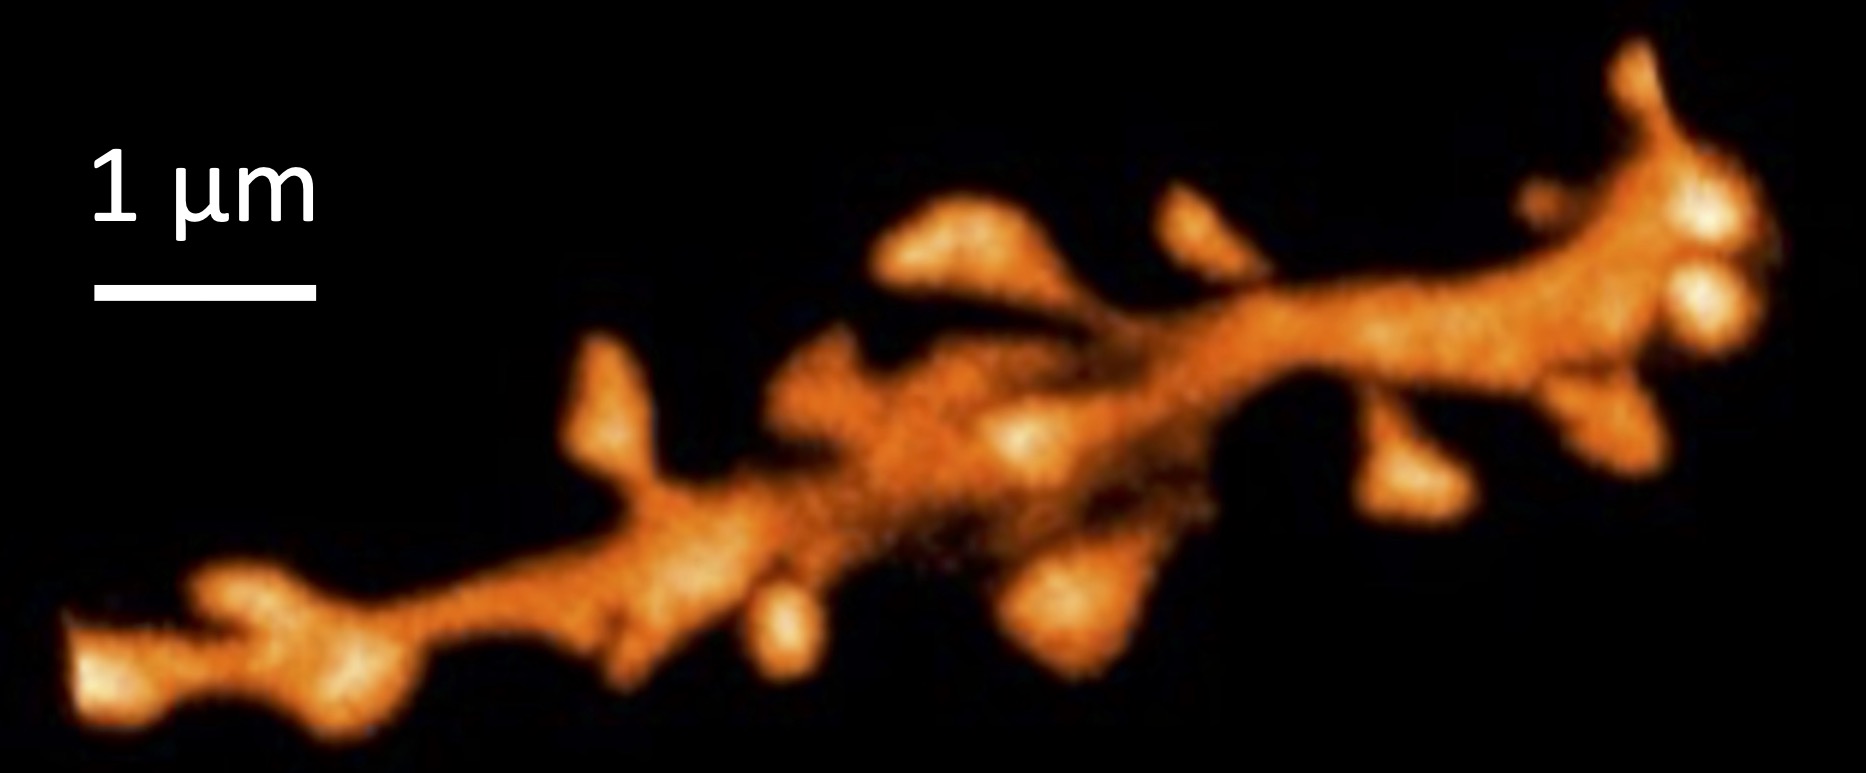

Nous recherchons, en manipulant pharmacologiquement la HSP, à élucider la relation entre la taille de la PSD, la perte synaptique et la fonction neuronale dans un modèle murin de maladie d’Alzheimer, à l’aide de techniques fonctionnelles (électrophysiologie) et structurelles (marquages immunofluorescents de la PSD, des épines dendritiques et des versants pré et post-synaptiques à l’aide de la microscopie super-résolutive STED).